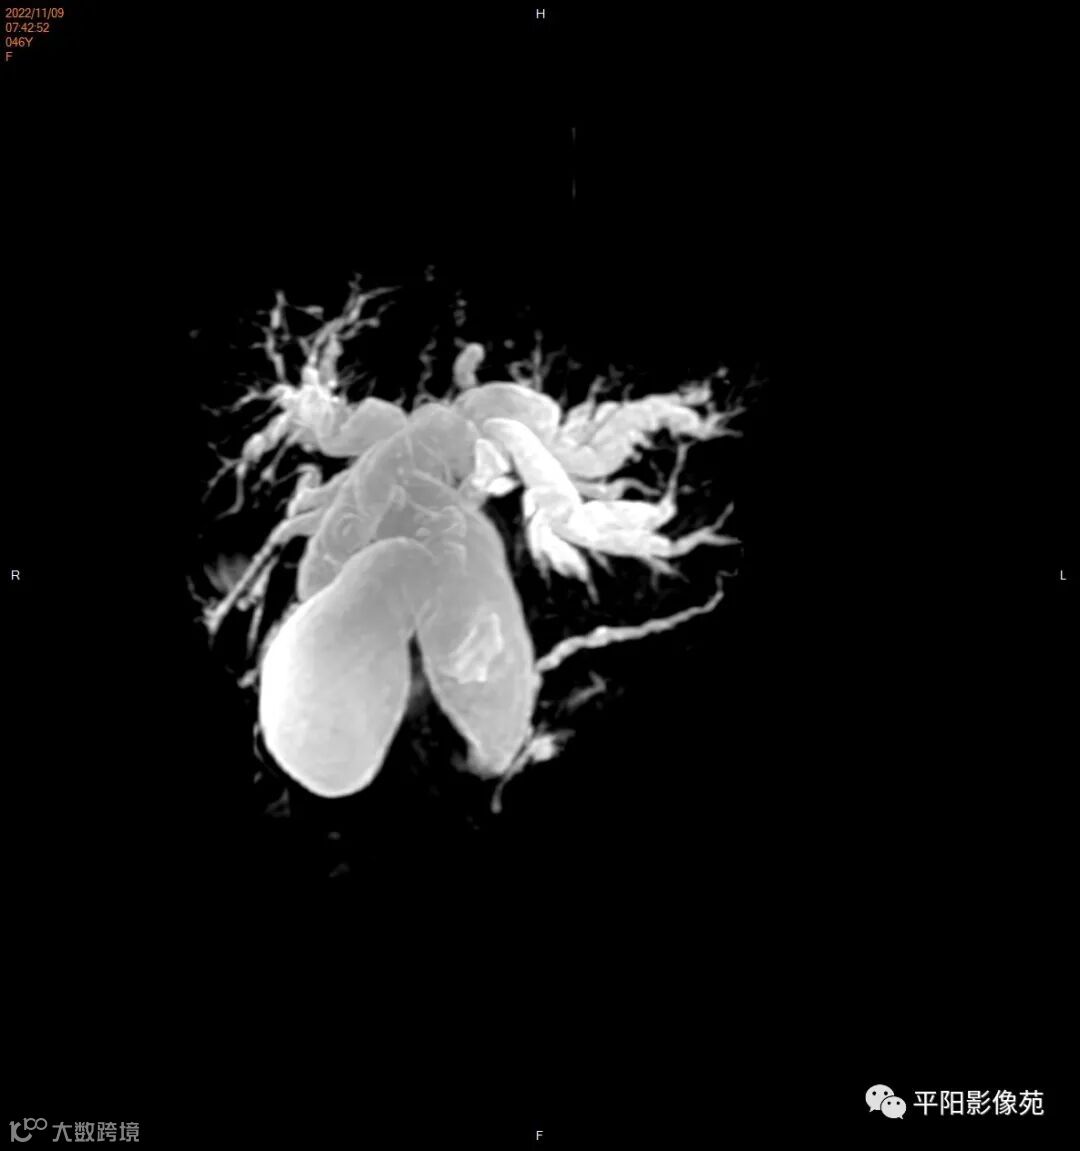

MR